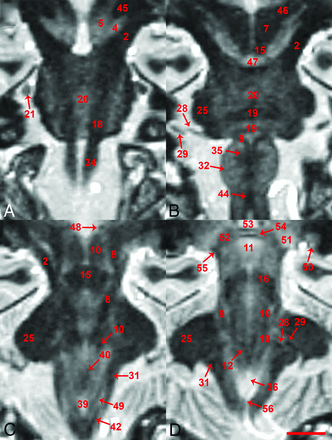

The FGATIR sequence provided novel MR imaging–derived contrast throughout the in vivo brain stem and allowed the direct identification of many small functionally important structures. Structure identification by 2 neuroradiologists was facilitated by 3-plane cross-referencing. Selected serial axial images illustrate contrast resolution of internal brain stem anatomy at canonical levels (Fig 1). Selected coronal and sagittal images also reveal excellent contrast resolution of internal brain stem anatomy (Figs 2 and 3, respectively). Such longitudinal images demonstrate the superior-inferior course of several brain stem pathways and the potential for the 0.8-mm isotropic FGATIR to enhance our understanding of the 3D organization of the brain stem. Videos of axial, coronal, and sagittal images through the brain stem are provided to interested readers on-line (On-line Videos 1–3).

Anterior-to-posterior coronal in vivo MR images for the brain stem including 13.5-, 9-, 4.5-, and 1.5-mm anterior and parallel to the rhomboid fossa (A–D, respectively). A 26-year-old healthy control female subject, 0.8-mm isotropic resolution, 9 individual datasets coregistered and averaged, 2× imaging sessions, ∼2-hour 15-minute total scan time (scale bar = 5 mm). Note this orientation is parallel to the long axis of the brain stem, but not orthogonal to the intercommissural plane. Please see the Table and the Results section for explanation of labeled structures.

Labeling in the figures emphasizes unambiguous structures that can be identified well on the images. Most of these labeled structures are well-known to clinicians familiar with brain stem anatomy (eg, the medial longitudinal fasciculus). Directly labeled visible structures also can be used to generate more exact indirect localization for other bordering internal brain stem structures. Figure 4 provides a highly detailed example of this approach for the inferior midbrain where the likely positions of multiple additional structures can be estimated relative to the borders and anatomic spaces formed between the medial longitudinal fasciculus, medial lemniscus, and decussation of the superior cerebellar peduncles. Annotation at this level of detail with descriptions of functional relevance is possible throughout the brain stem, but is beyond the scope of this initial report. Other selected examples of indirect localization that may be of general interest include the oculomotor complex (bright region posteromedial to the central tegmental tract in Fig 1A), pedunculopontine nucleus (bright region medial to the medial lemniscus and lateral to the decussation of the superior cerebellar peduncles, in Fig 1B), locus coeruleus (bright region posterior to the central tegmental tract and medial to the superior cerebellar peduncle in Fig 1C), and facial nucleus (bright region posterolateral to the central tegmental tract and medial to the cerebellar peduncles in Fig 1F). An inferior notch along the medial aspect of the left middle cerebellar peduncle with gray matter signal intensity in Fig 2D is the cochlear nucleus.

There also are subtle features in the images that are difficult to assign with certainty (and sometimes only visualized on 1 side) that likely correspond to specific structures better resolved with postmortem MR microscopy53 and histology atlases.48⇓–50 Limited visualization may be from partial volume effects due to the small size of the structures relative to 0.8-mm isotropic voxels and/or less contrast relative to surrounding nervous tissue. On the right side of Fig 1B, there is an arc-like medially concave dark structure oriented anterior-posterior, consistent with the expected location of the left oculomotor nerve. In Fig 1C, -D, the tectospinal tract appears as a faint dark dotlike structure anterior to the medial lemniscus, particularly on the left side. In Fig 1E, the left tectospinal tract is more obvious, but there is marked asymmetry compared with the subject’s right side. Also, in Fig 1E, the indistinct anterior margin of the medial lemniscus may represent the anteromedial continuation of the trapezoid body. In Fig 2D, an intermediate signal intensity line oriented inferomedial to superolateral, dividing the area postrema (on the right side of the image), may be the sulcus limitans. Some structures also are better recognized when the imaging plane is transverse to the structure. For example, the facial nerve in the lateral midpons is difficult to appreciate in the axial plane (Fig 1F), but better resolved in the coronal plane (Fig 2D).